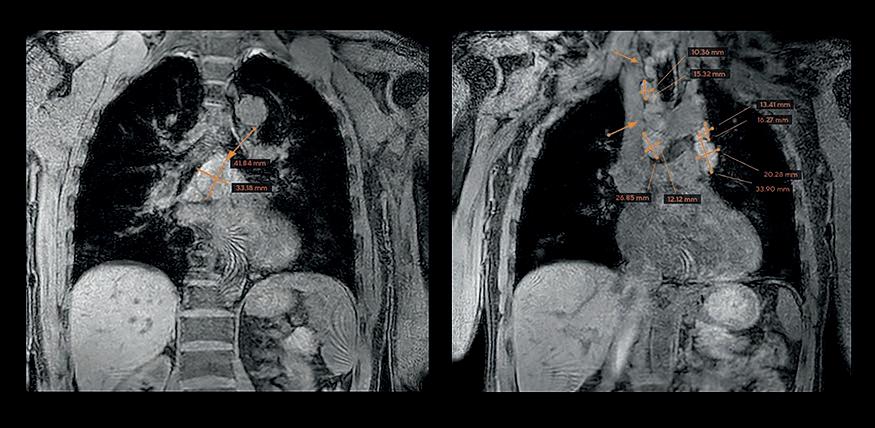

Ganzkörper-MRT in der radiologischen Privatpraxis Dr. med. Michael J. Ho

Dr. med. Michael J. Ho setzt die Ganzkörper-MRT bereits erfolgreich als Früherkennungsuntersuchung ein. Er ist Facharzt für Radiologie und Experte für die Bildgebung der peripheren Nerven.

In seiner Privatpraxis im Herzen der Altstadt von Münster bietet er Ihnen das gesamte Spektrum moderner MRTDiagnostik sowie MRT-geführte Interventionen an. Zusätzlich profitieren Sie als Patientin bzw. als Patient von dem national und international tätigen ARISTRANetzwerk, das aus kompetenten und erfahrenen Ärztinnen und Ärzten besteht.